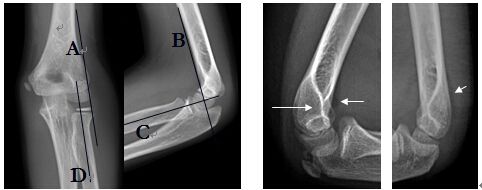

因肘部創(chuàng)傷性關(guān)節(jié)炎而出現(xiàn)尺神經(jīng)受壓,在尺側(cè)腕屈肌兩頭之間有一增厚的纖維帶,壓迫尺神經(jīng),稱之為肘管綜合征。在肱骨內(nèi)上髁與尺骨鷹咀之間有一弧形窄而深的骨溝,有深筋膜橫架于上,形成一骨性纖維鞘管,即尺神經(jīng)溝,也稱肘尺管。管內(nèi)為尺神經(jīng)及尺側(cè)上副動(dòng)、靜脈。